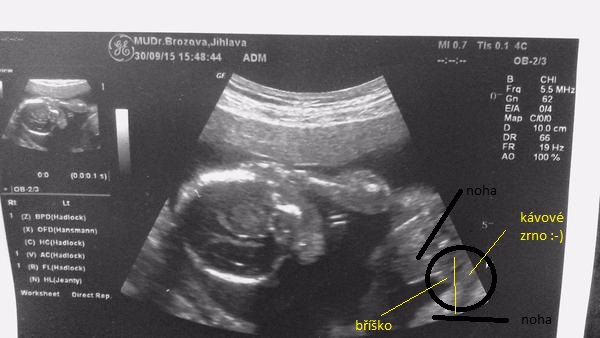

Tak ještě jak to vidím já 🙂, třeba to i pomůže někomu se lépe orientovat ve vlastních fotkách 😉

tady je hezky znázornění,ze může byt pindik i kavove zrno,😃myslím tím ty kuličky. ..ale říkáte ze je to kluk,tak to kluk je,myslím ze je to moc hezká fotecka 👍😉